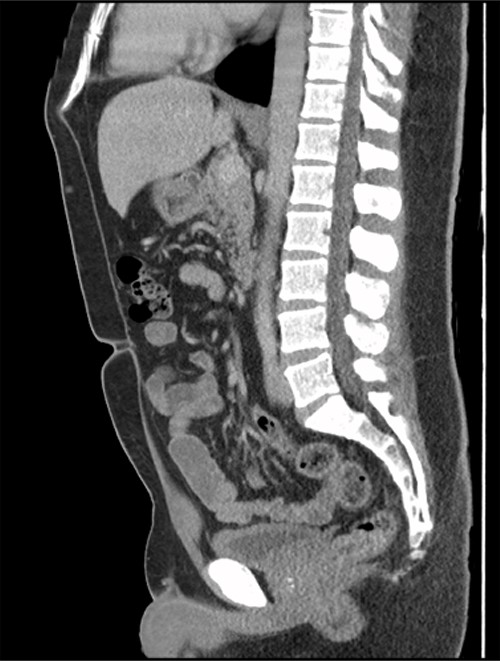

A 41-year-old, previously well, male presented to the emergency department with lower abdominal pain, pyrexia with a temperature of 38.2°C and a palpable suprapubic mass. His relevant background history included an uneventful laparoscopic appendicectomy 2 years prior for acute appendicitis, insulin independent type 2 diabetes and hypertension. He presented with raised inflammatory markers and computed tomography (CT) showing a well circumscribed central pelvis lesion that appeared concerning for a urachal malignancy (Fig. 1). This lesion was closely associated with the dome of the bladder (Fig. 2). This supracystic lesion measured 58 mm × 56 mm with central cystic component of 15 mm in diameter, and contained a 11 mm central calcification. Further characterization with magnetic resonance imaging showed possible extension of this mass to the rectus abdominis without significant lymphadenopathy (Fig. 3). Flexible cystoscopy only found inflammation at the dome. As urachal malignancy could not be unequivocally excluded on imaging studies alone, following multidisciplinary discussion, the decision was made to perform an excision of this lesion.

Sagittal CT cystogram. Arrowhead indicates involvement of anterior abdominal wall. Arrow indicates association of lesion with the dome of the bladder.